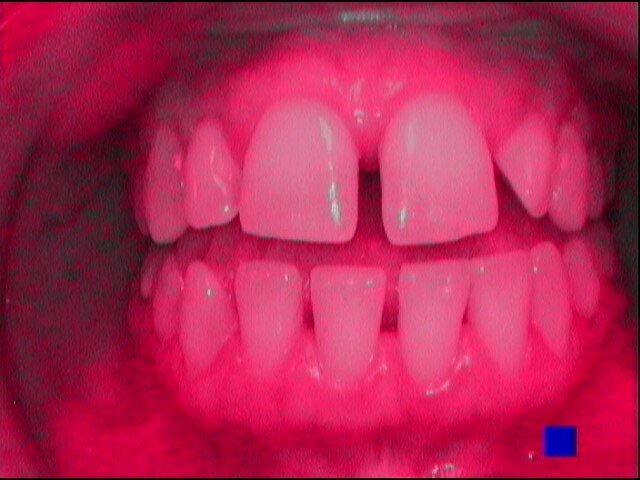

Si presenta alla nostra attenzione un giovane paziente di anni 26, non fumatore, in apparente salute sistemica, in terapia ortodontica con mascherina invisibile lamentando un cattivo odore dell’allineatore, percepito in maniera fastidiosa grazie all’utilizzo obbligato della mascherina per le norme di sicurezza anti-Covid 19. Invitiamo il paziente a rimuovere le mascherine al fine di eseguire un esame obiettivo intra-orale e valutare le condizioni di integrità degli allineatori.

Il paziente ha un buon controllo del biofilm batterico. Viene consigliato il controllo dell’alito attraverso il test organolettico sniff test e il paziente si rassicura poiché non avverte cattivo odore. Chiediamo al paziente in che modo igienizza invece il dispositivo ortodontico e ricordiamo al paziente di aver consigliato l’utilizzo della compressa igienizzante. Il paziente ci riferisce di non aver usato la pastiglia poiché divide l’abitazione con suoi colleghi universitari e non ha piacere di immergere il dispositivo in un bicchiere d’acqua con l’aggiunta della pastiglia igienizzante, poiché lo trova sconveniente e se ne vergogna. Il paziente chiede se può disinfettarla facendola bollire (Figg. 1-9).